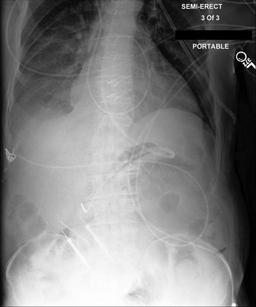

Curation of imaging datasets

CXR datasets [36] often contain multiple image acquisitions in a single visit due to data quality issues such as a limited field-of-view or scanning the wrong body part (Figure A.7). Unlike [9, 32, 81], we conduct curation to choose higher quality images among the potential candidates instead of performing a random selection. For this step, a separate BioViL-T is trained on ‘clean’ studies with single acquisitions and later used in a zero-shot setting to detect out-of-distribution samples [26, 27] arising from the re-imaging process. The candidate is selected as follows: for a margin . This approach is applied to enhance the quality of the temporal classification dataset given its limited size.

A.4 Data curation of imaging datasets

Large datasets often contain instances that are mislabelled or out of distribution [35]. We used BioViL-T to perform pairwise ranking of instances in MIMIC-CXR (Section 3.3, ) and selected representative examples found in the dataset. Our method is able to select the most appropriate image for a range of different image-acquisition or image-processing issues (Figure A.7).

We found that many lateral acquisitions in the dataset were unexpectedly labelled as frontal (Figure 7(a)). Some images contained only noise (Figure 7(b)), non-human samples (Figures 7(d) and 7(e)) or incorrect anatomy (Figure 7(g)). Often, acquisitions with an incomplete field of view (FOV) (i.e., the lungs are not completely visible) were repeated (Figure 7(c)). Lastly, post-processed images were detected by the algorithm such as contrast-enhanced scans (Figure 7(i)) that are not often used for diagnostic purposes in clinical practice.